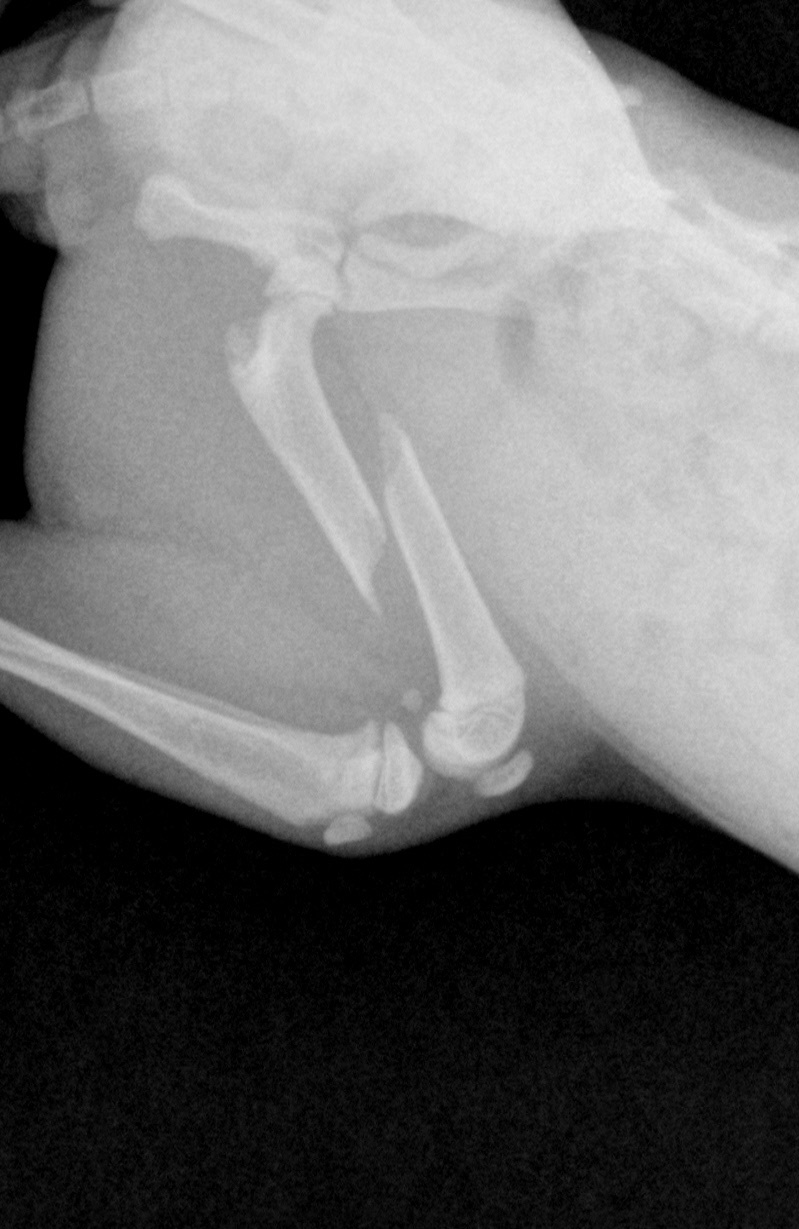

Afficher la pièce jointe 598417 voila le resultatAfficher la pièce jointe 598421 du chaton que j'ai recupere mercredi

ha oui on voit la fracture